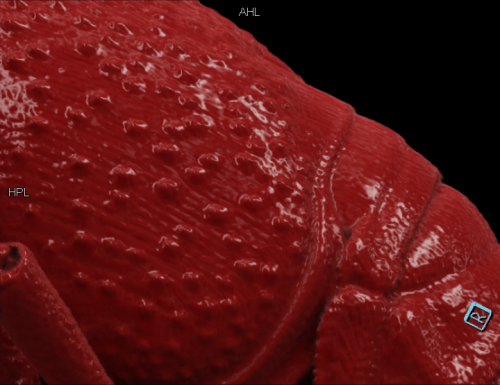

局部特写,cVRT 重建(作者供图)

小龙虾局部特写,cVRT 重建,空间分辨率为 27 个线对(作者供图)